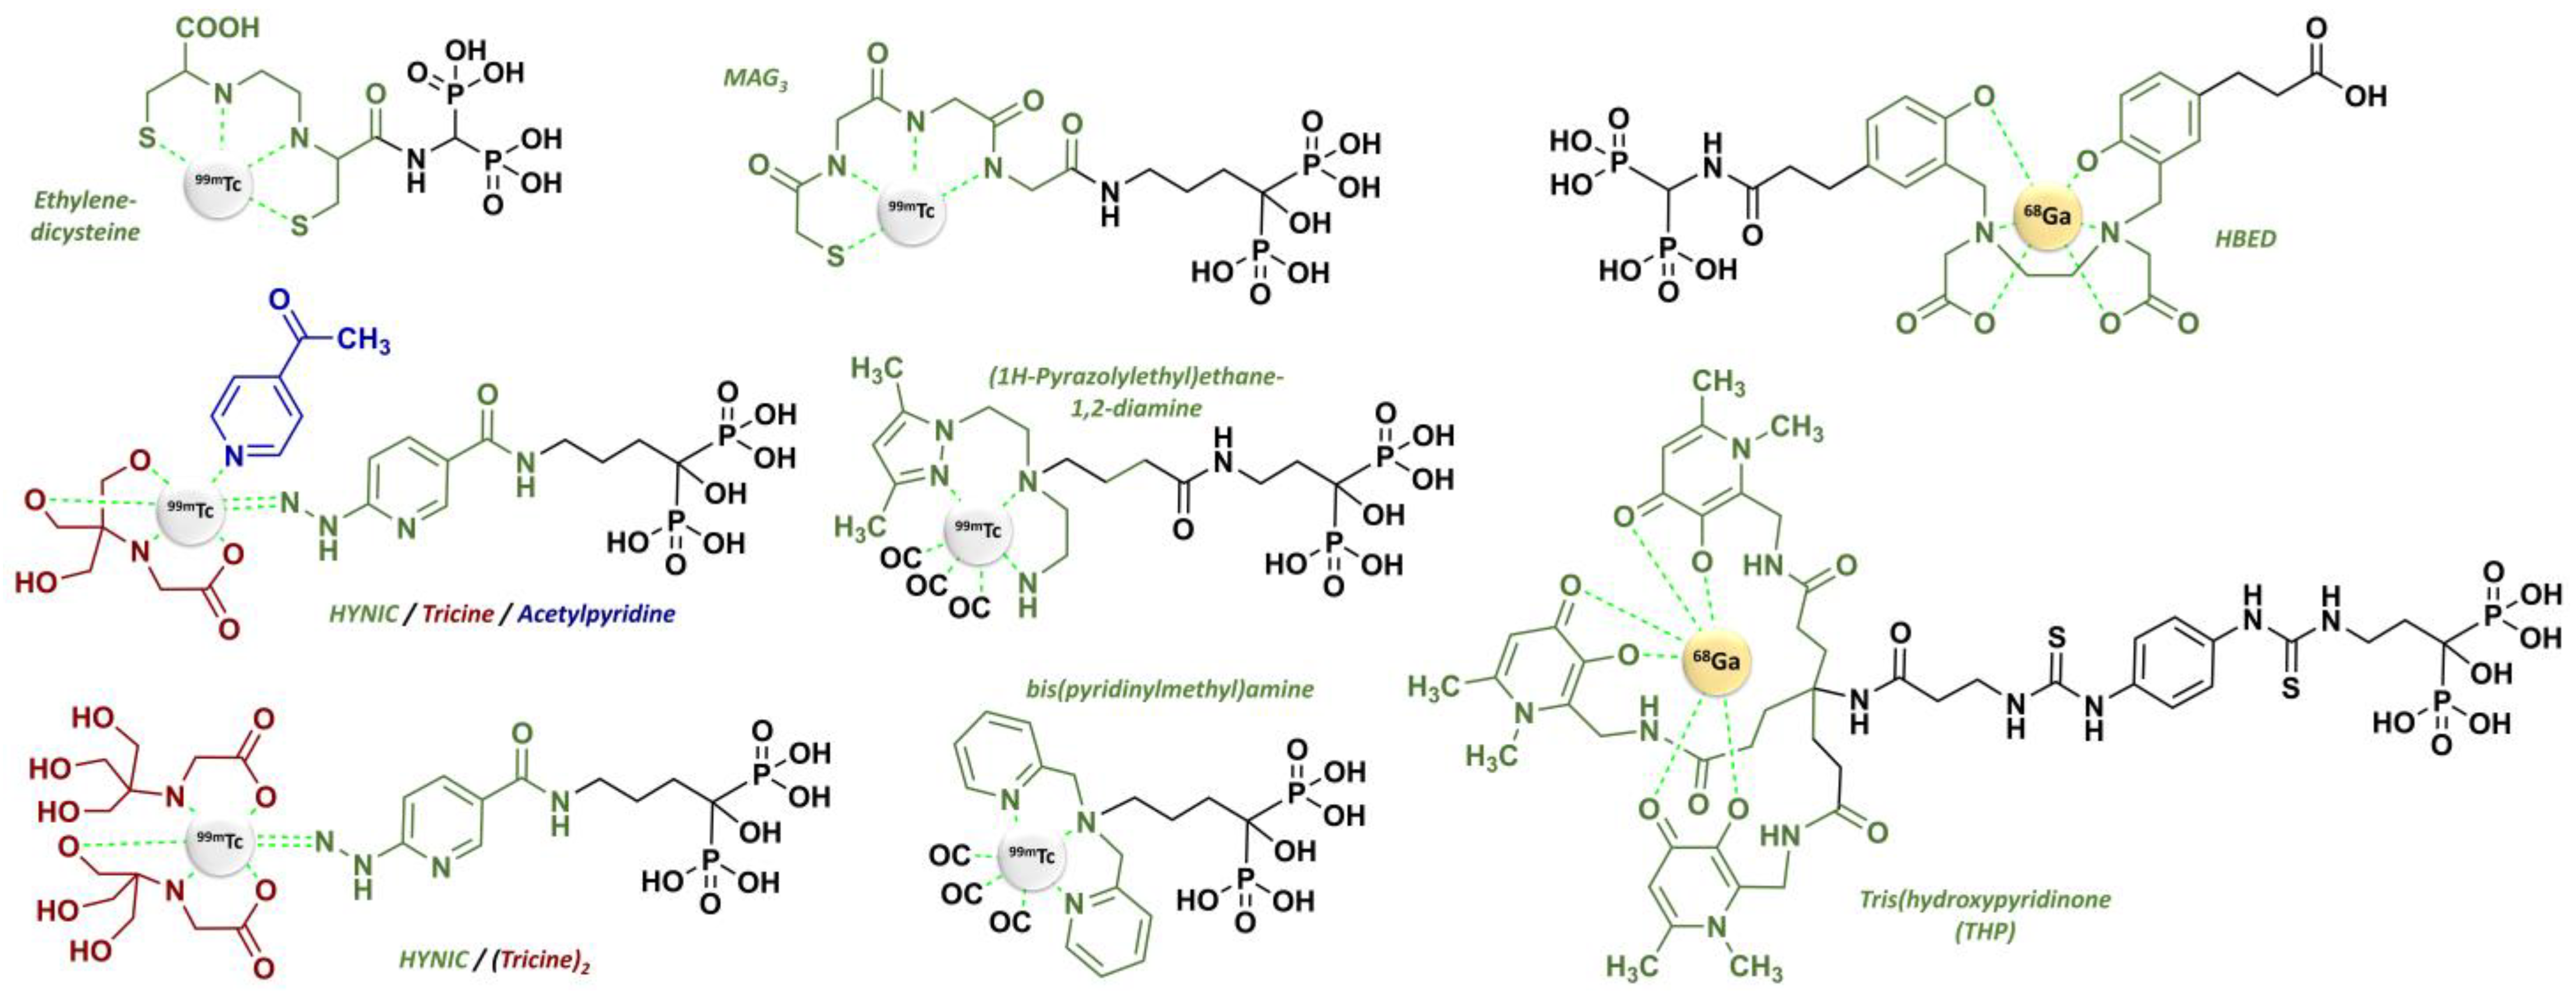

- Specific targeting based on a vector molecule with bone tropism: in scintigraphic imaging, medronate (MDP) [97] and oxidronate (HMDP) [98,99] were among the first bisphosphonates to be used as bone scintigraphy imaging vectors on humans after the pioneering application of [99mTc]Tc-etidronate [100,101,102,103] (Figure 5). These two compounds are characterized by their simple chemical structures, which do not contain dedicated chelation sites. Although their formulation in single-vial cold kits for radiopharmaceutical preparation makes 99mTc radiolabeling simple and ensures high radiochemical purity levels, [99mTc]Tc-MDP and [99mTc]Tc-HMDP complexes do not form a single defined chemical entity but are rather structured into a mixture of monomers, oxo-bridged dimers and oligomeric clusters of varying sizes, featuring diverse technetium-oxo core arrangements, oxidation states and ligand coordination numbers [104] with a composition that varies according to pH, technetium concentration and oxygen amount [105]. Lastly, the phosphonate groups of MDP and HMDP (as well as the hydroxyl group of HMDP) serve both as coordination sites with 99mTc and as recognition sites for the bone mineral matrix. Consequently, the bone affinity of the corresponding 99mTc complexes is intrinsically reduced [106]. Even so, these radiopharmaceuticals remain reference bone scintigraphy agents, either in oncology for cancer staging [107,108] and therapeutic response evaluation [109,110,111] or in benign bone disorders such as Paget disease [112,113] or primary hyperparathyroidism [114,115]. Interestingly, 99mTc-radiolabeled butedronate (2,3-dicarboxypropane-1,1-diphosphonate, DPD, Figure 5) [116] is another SPECT imaging agent with the same indications as [99mTc]Tc-MDP and [99mTc]Tc-HMDP but also has a particular role in the detection of cardiac amyloidosis [117,118,119]. Concerning therapy, a bisphosphonate-related derivative with an ethylenediamine tetraphosphonate structure (EDTMP, also named lexidronam) radiolabeled with 153Sm (t1/2 = 1.9 days; Eβ-max = 0.81 MeV) has also been used since the late 1980s [120,121] for the relief of pain resulting from bone metastases; two clinical trials demonstrated its efficacy in this indication versus the placebo and its improved toxicity profile compared to 89Sr and 32P [122,123]. Notably, etidronate was also selected for radionuclide therapy applications after radiolabeling with beta minus-emitting rhenium isotopes, either 186Re or 188Re [9,10,11,12,13,14,15,16,17,18,19,20,21], but with rather limited clinical use.

2.3. From Standard Bisphosphonates to Bifunctional Derivatives Optimized for Nuclear Medicine